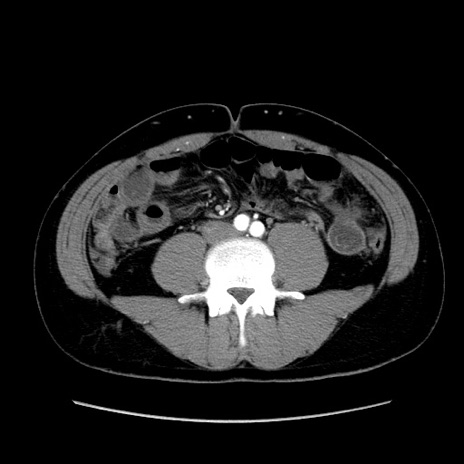

症例36(横断像)

【症例】20歳代 男性

【主訴】心窩部痛

【現病歴】今朝より上腹部痛あり。一旦軽快していたが再度出現したため救急要請。昨日夕に白身の魚を含む刺身を食べた。

【身体所見】BP 136/89mmHg、HR 74/min、BT 37.0℃、腹部:膨満、軟、心窩部に圧痛あり。反跳痛なし、筋性防御なし、腸雑音やや亢進あり。

【データ】WBC 17700、CRP 0.48